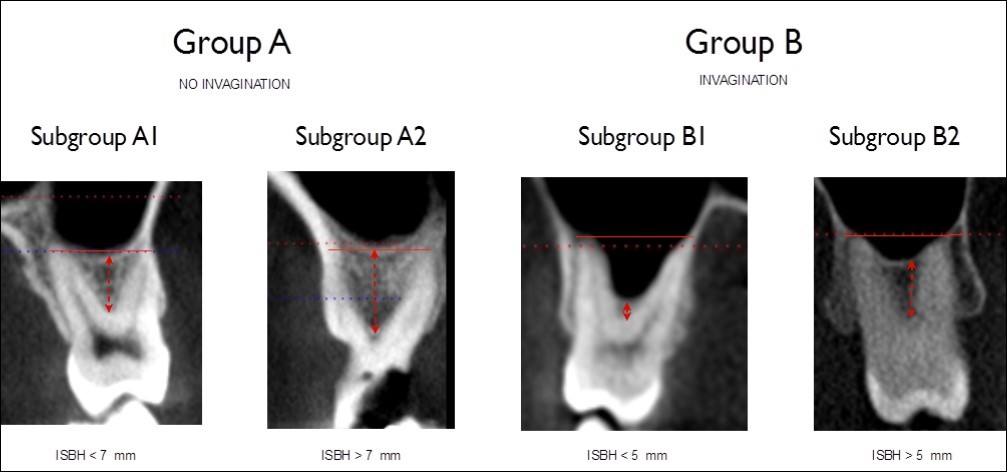

The molar findings regarding interradicular septum bone height (ISBH) were further classified into subgroups for each of the two main groups as follows:

1. Subgroup A1: ISBH < 7 mm

2. Subgroup A2: ISBH > 7 mm

3. Subgroup B1: ISBH < 5 mm

4. Subgroup B2: ISBH > 5 mm

Figure 3 presents examples of each of the four categories.

Figure 3.Classification in four different categories for molars, based on sinus invagination and interradicular bone septum height (ISBH).